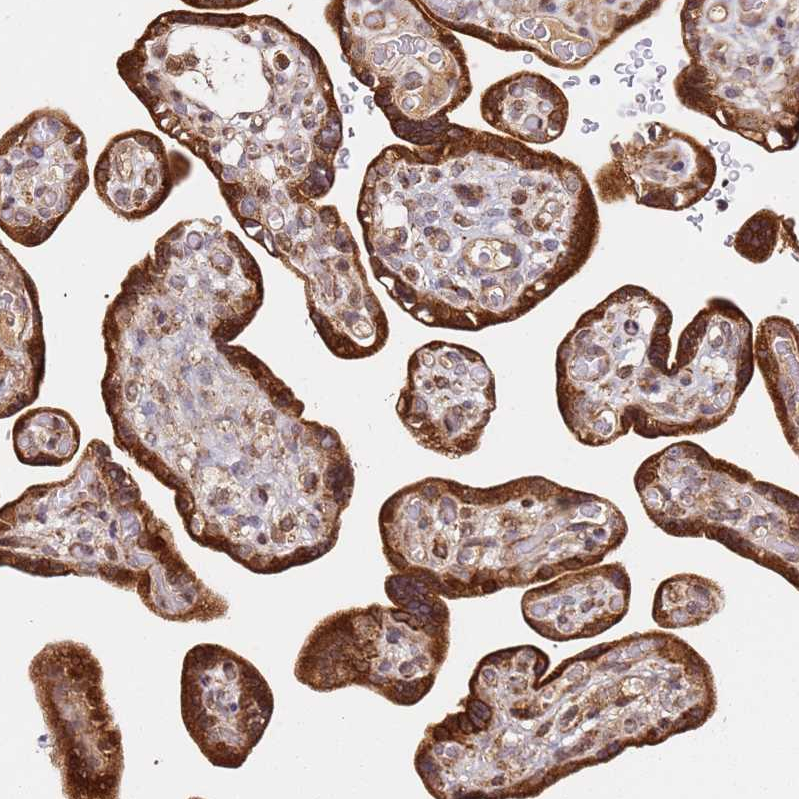

Immunohistochemical staining of human pancreas shows strong cytoplasmic and nuclear positivity in exocrine glandular cells.